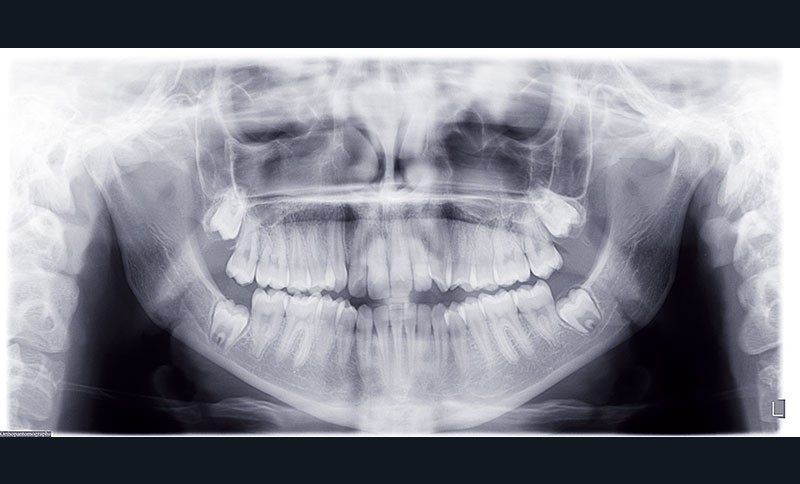

Cas clinique n° 2 : Motion Classe III

Nous sommes en présence d’une patiente en fin de croissance faciale, âgée de 16 ans. Elle présente une classe III dentaire et squelettique associée à une asymétrie faciale de type latérognathie mandibulaire avec déviation des points interincisifs et déviation du menton vers la gauche.

2e phase : mise en place du système multibague Carriere SLX (fig. 7 à 9)

Nous continuons le port des élastiques…